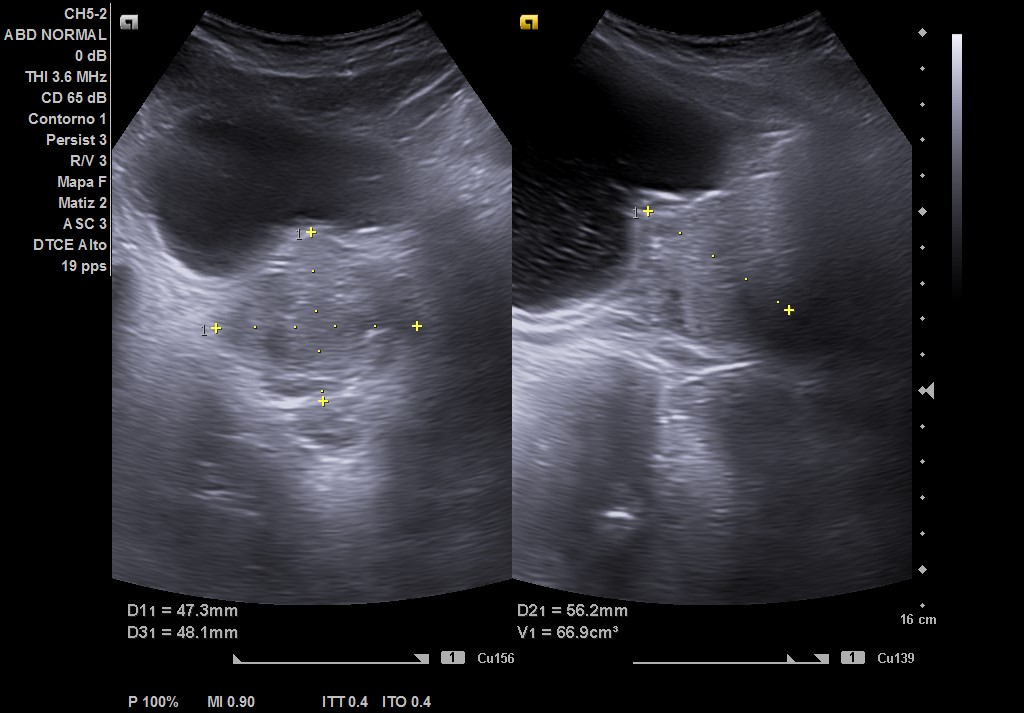

Ecografía tras ingerir 1 litro de agua y sin orinar posteriormente, con sonda convex: se visualiza vejiga repleccionada hasta 2 cm del ombligo, con > 550 cc (difícil de cuantificar por gran tamaño). Residuo postmiccional 525 cc, paredes de vejiga con signos de lucha, divertículo e imagen de «centelleo» en desembocadura de uréter derecho, pero sin afección del jet ureteral ipsilateral. Próstata de 67 cc aproximadamente, que protruye en vejiga. Riñones con ecoestructural normal sin dilatación en vía excretora.